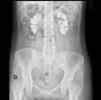

El electrocardiograma mostraba ritmo sinusal, con elevación de ST de 1mm en todas las derivaciones. La radiografía de tórax fue normal. En la radiografía simple de abdomen se comprobaron extensas calcificaciones renales bilaterales (fig. 1). Tras corrección de hipocalcemia, hipomagnesemia y acidosis metabólica la paciente fue dada de alta, sin incidencias relevantes durante el ingreso. Los valores analíticos al alta fueron creatinina 3,6mg/dl; sodio 142mmol/l; potasio 4,4mmol/l; pH 7,43; bicarbonato 24,6mmol/l; calcio 8,6mg/dl; calcio iónico corregido 1,16mmol/l; fósforo 2,9, PTHi 103ng/ml y magnesio 1,9mg/dl. El tratamiento al alta fue: carbonato cálcico 2,5 g cada 8 h; calcitriol 0,5 mcg/día; bicarbonato sódico 1 g/día y suplementación de potasio y magnesio oral.